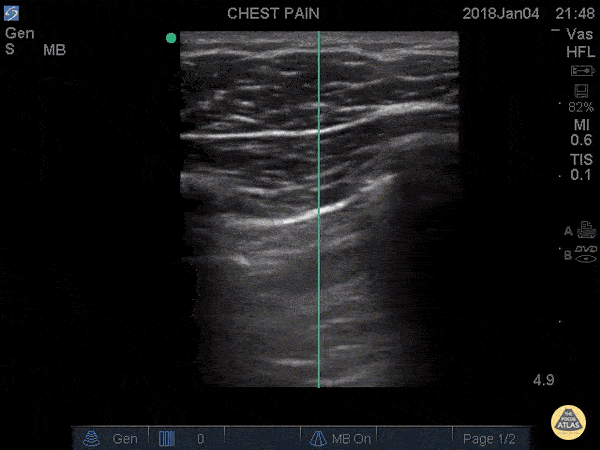

IS THERE LUNG SLIDING?

This profile is characterised by absent lung sliding and present A-lines. The finding of dynamic lung sliding rules out the presence of pneumothorax. In addition, the finding of the B lines artefact indicates indemnity of both pleural layers and rules out the presence of pneumothorax.

When there is a pneumothorax, the pleural layers are separated by air. Ultrasound waves are reflected at the encounter of the parietal pleura, which lies upon the air of the pneumothorax itself. Therefore, movement of the visceral pleura and lung deep to the pneumothorax cannot be seen, leading to loss of the typical shimmering, dynamic appearance.

ABSENT LUNG SLIDING

Although it is usually a key feature of pneumothorax, the absence of dynamic lung sliding lacks specificity and can also be found in other conditions such as apnea, atelectasis, bullae, chronic airflow limitation, pleurodesis, inflammatory adherences, fibrosis, right main-stem intubation, oesophagal intubation and cardiopulmonary arrest.

LUNG POINT

Conversely, the lung point sign is pathognomonic and 100% specific for pneumothorax. It represents the transition point where a normal lung gives way to pneumothorax: sliding is present on one side of the image while absent on the other. Additionally, the lung point indicates pneumothorax volume: moderate if anterior, massive if posterior or absent. Lateral lung points correlate with a 90% need for drainage versus 8% with anterior lung-point (11).

The M mode is far from essential but can be helpful in the interpretation if you struggle to identify sliding in B-Mode. A ‘seashore image’ will be seen in the normal lung, whereas a ‘barcode image’ will appear in absence of lung sliding. Remember, absent lung sliding by itself is not diagnostic of pneumothorax.